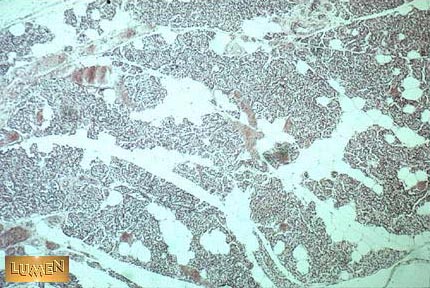

Q1 What hormone is the primary product of this gland.

Answer 1

PTH

Answer 2

Increases renal tubular absorption of Calcium

Increases intestinal uptake of Calcium

Increases bone resorption